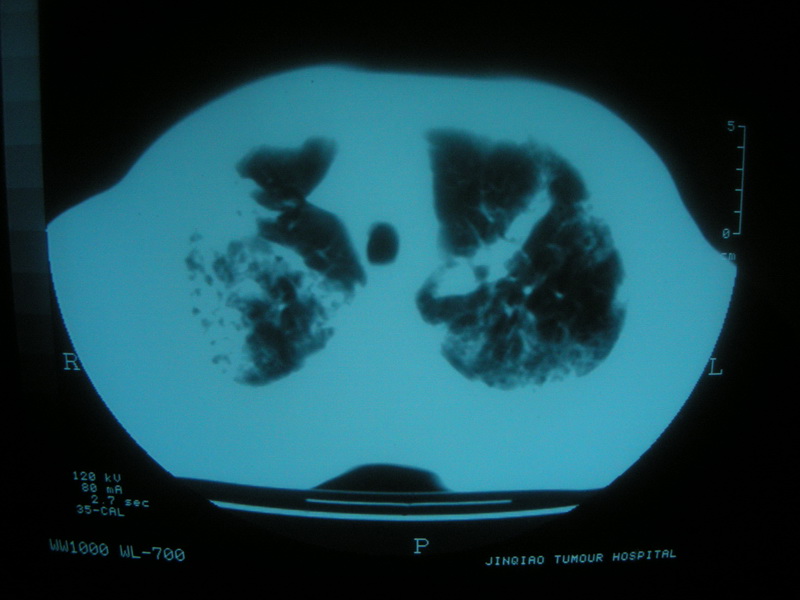

标题: CT11692:男,63岁,糖尿病史15年.抗炎治疗7天,病情 [打印本页]

标题: CT11692:男,63岁,糖尿病史15年.抗炎治疗7天,病情

请老师看看是结核还是炎症?

根据影像表现及临床符合结核感染。

双肺继发性肺结核伴感染!

双肺继发性肺结核伴支气管播散。